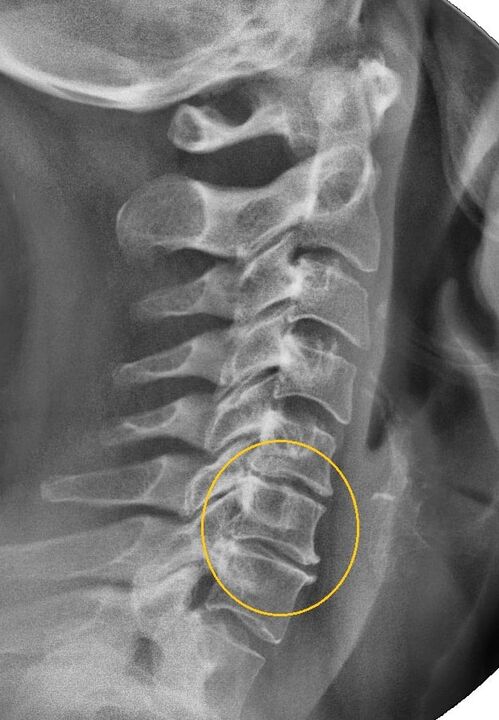

La procédure de diagnostic la plus informative est la radiographie. Les pathologies de 1er degré correspondent au 1er ou au 2ème stade radiologique. Les images obtenues visualisent les signes typiques de la maladie.

| Stades radiologiques de l'ostéochondrose cervicale du 1er degré | Signes caractéristiques |

|---|---|

| Étape 1 | Modifications mineures de la courbure de la colonne vertébrale dans la région cervicale, affectant un ou plusieurs segments |

| Étape 2 | Léger épaississement des disques intervertébraux, déformation des apophyses uncinées, redressement de la lordose, excroissances mineures des structures osseuses |